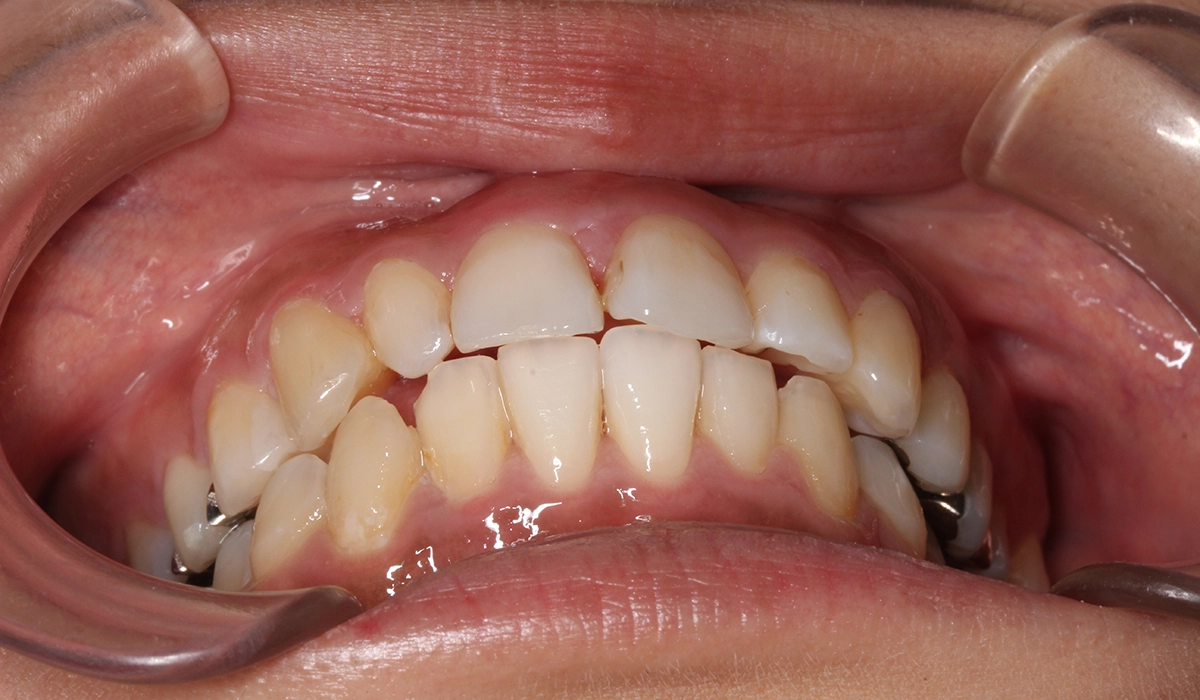

術前:正面

術後:正面